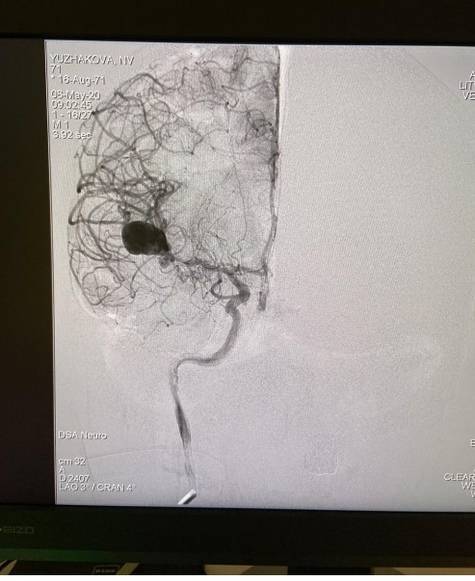

На снимках хорошо видно аневризму средней мозговой артерии. Проблемой для хирургов было то, что из-за своих размеров аневризма могла разорваться еще на пути хирургического доступа, а её клипирование привело бы к отключению важных артериальных ветвей, то есть было бы нарушено кровоснабжение мозга.

Контрольная трёхмерная ангиография показала, что операция прошла успешно.